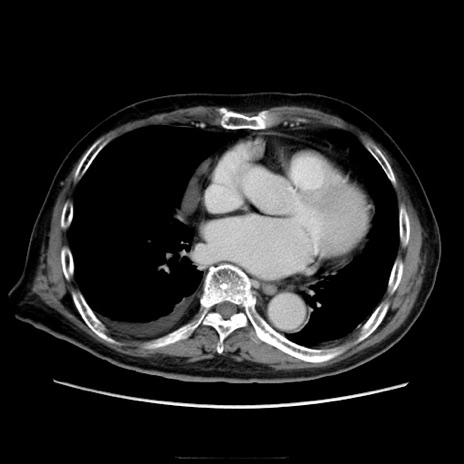

症例21(横断像)

【症例】70歳代男性

【主訴】腹痛

【現病歴】肝硬変・肝細胞癌にてかかりつけの方。約9時間前に食後より腹痛出現。症状が徐々に増悪し、嘔吐出現したため来院。

【既往歴】肝硬変、肝細胞癌(RFA、TACE後)

【身体所見】意識清明、表情苦悶様、BT 36℃、BP 129/78mmHg、P 88bpm、SpO2 97%(RA)、右上腹部から心窩部にかけて圧痛あり、反跳痛なし、筋性防御あり。

【データ】WBC 5800、CRP 0.16